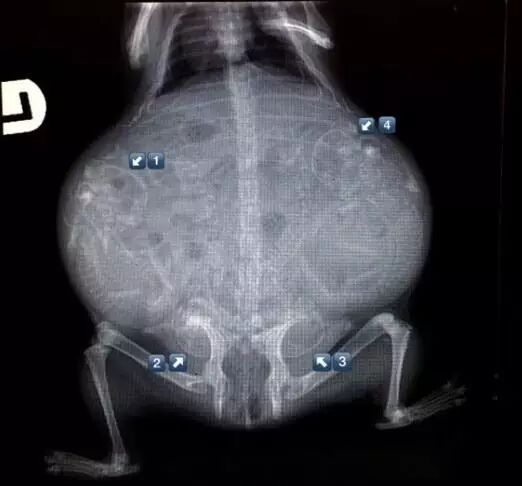

怀孕是一件神圣而又带有神秘色彩的事,她预示着新生命的来临。在动物世界,怀孕是怎样的一种奇迹,以下 14 种动物在怀孕期间的 X 线图片,我们可以通过全新的影像视角探查一番。

• 荷兰猪